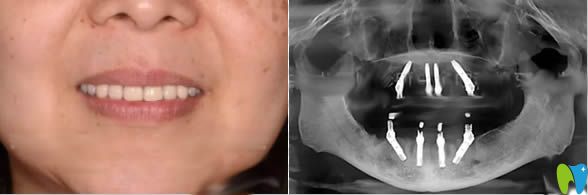

做完全口種植牙的照片及種牙后全景圖:

較后,說(shuō)下我做完種植牙的感受吧,種牙前很是緊張,種牙過(guò)程的不適感可以忍受,種完后感覺(jué)像真牙一樣,但就是價(jià)格貴。具體宏康口腔科怎么樣,我個(gè)人覺(jué)得這家還是很靠譜的,這只是我個(gè)人的想法,大家可以參考哈!